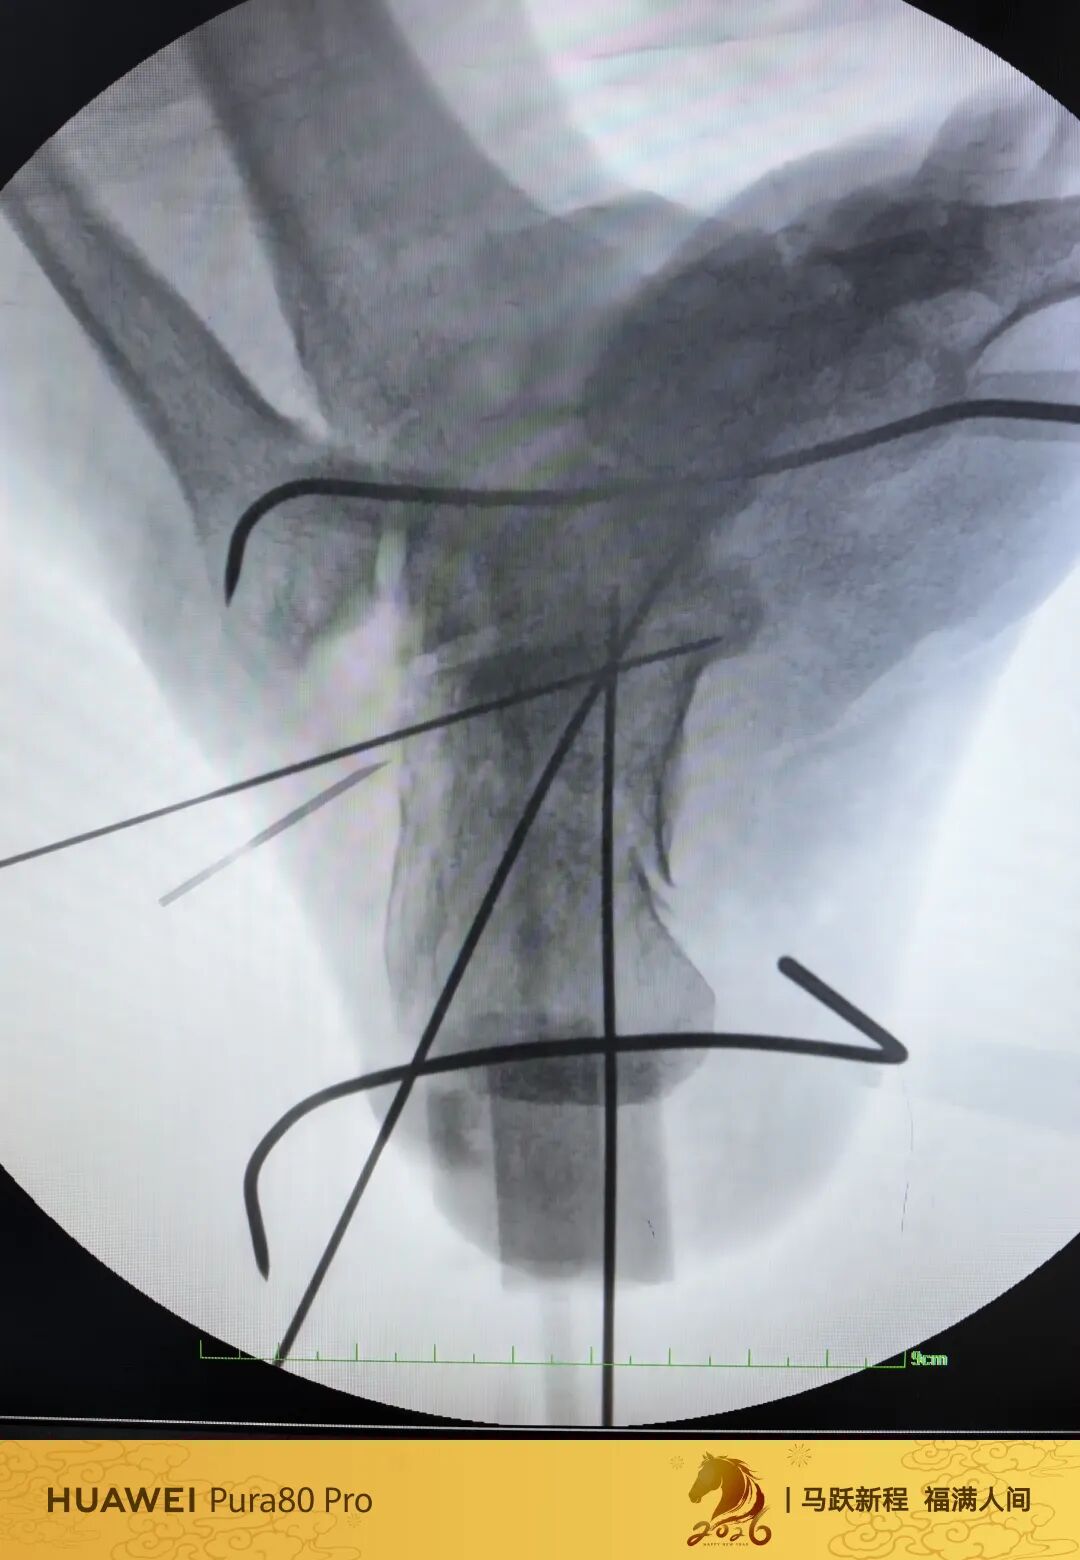

第60例跟骨微创了,虽然已经彻底放手,尽量只动嘴,但还是有小问题小瑕疵,无法完全避免。